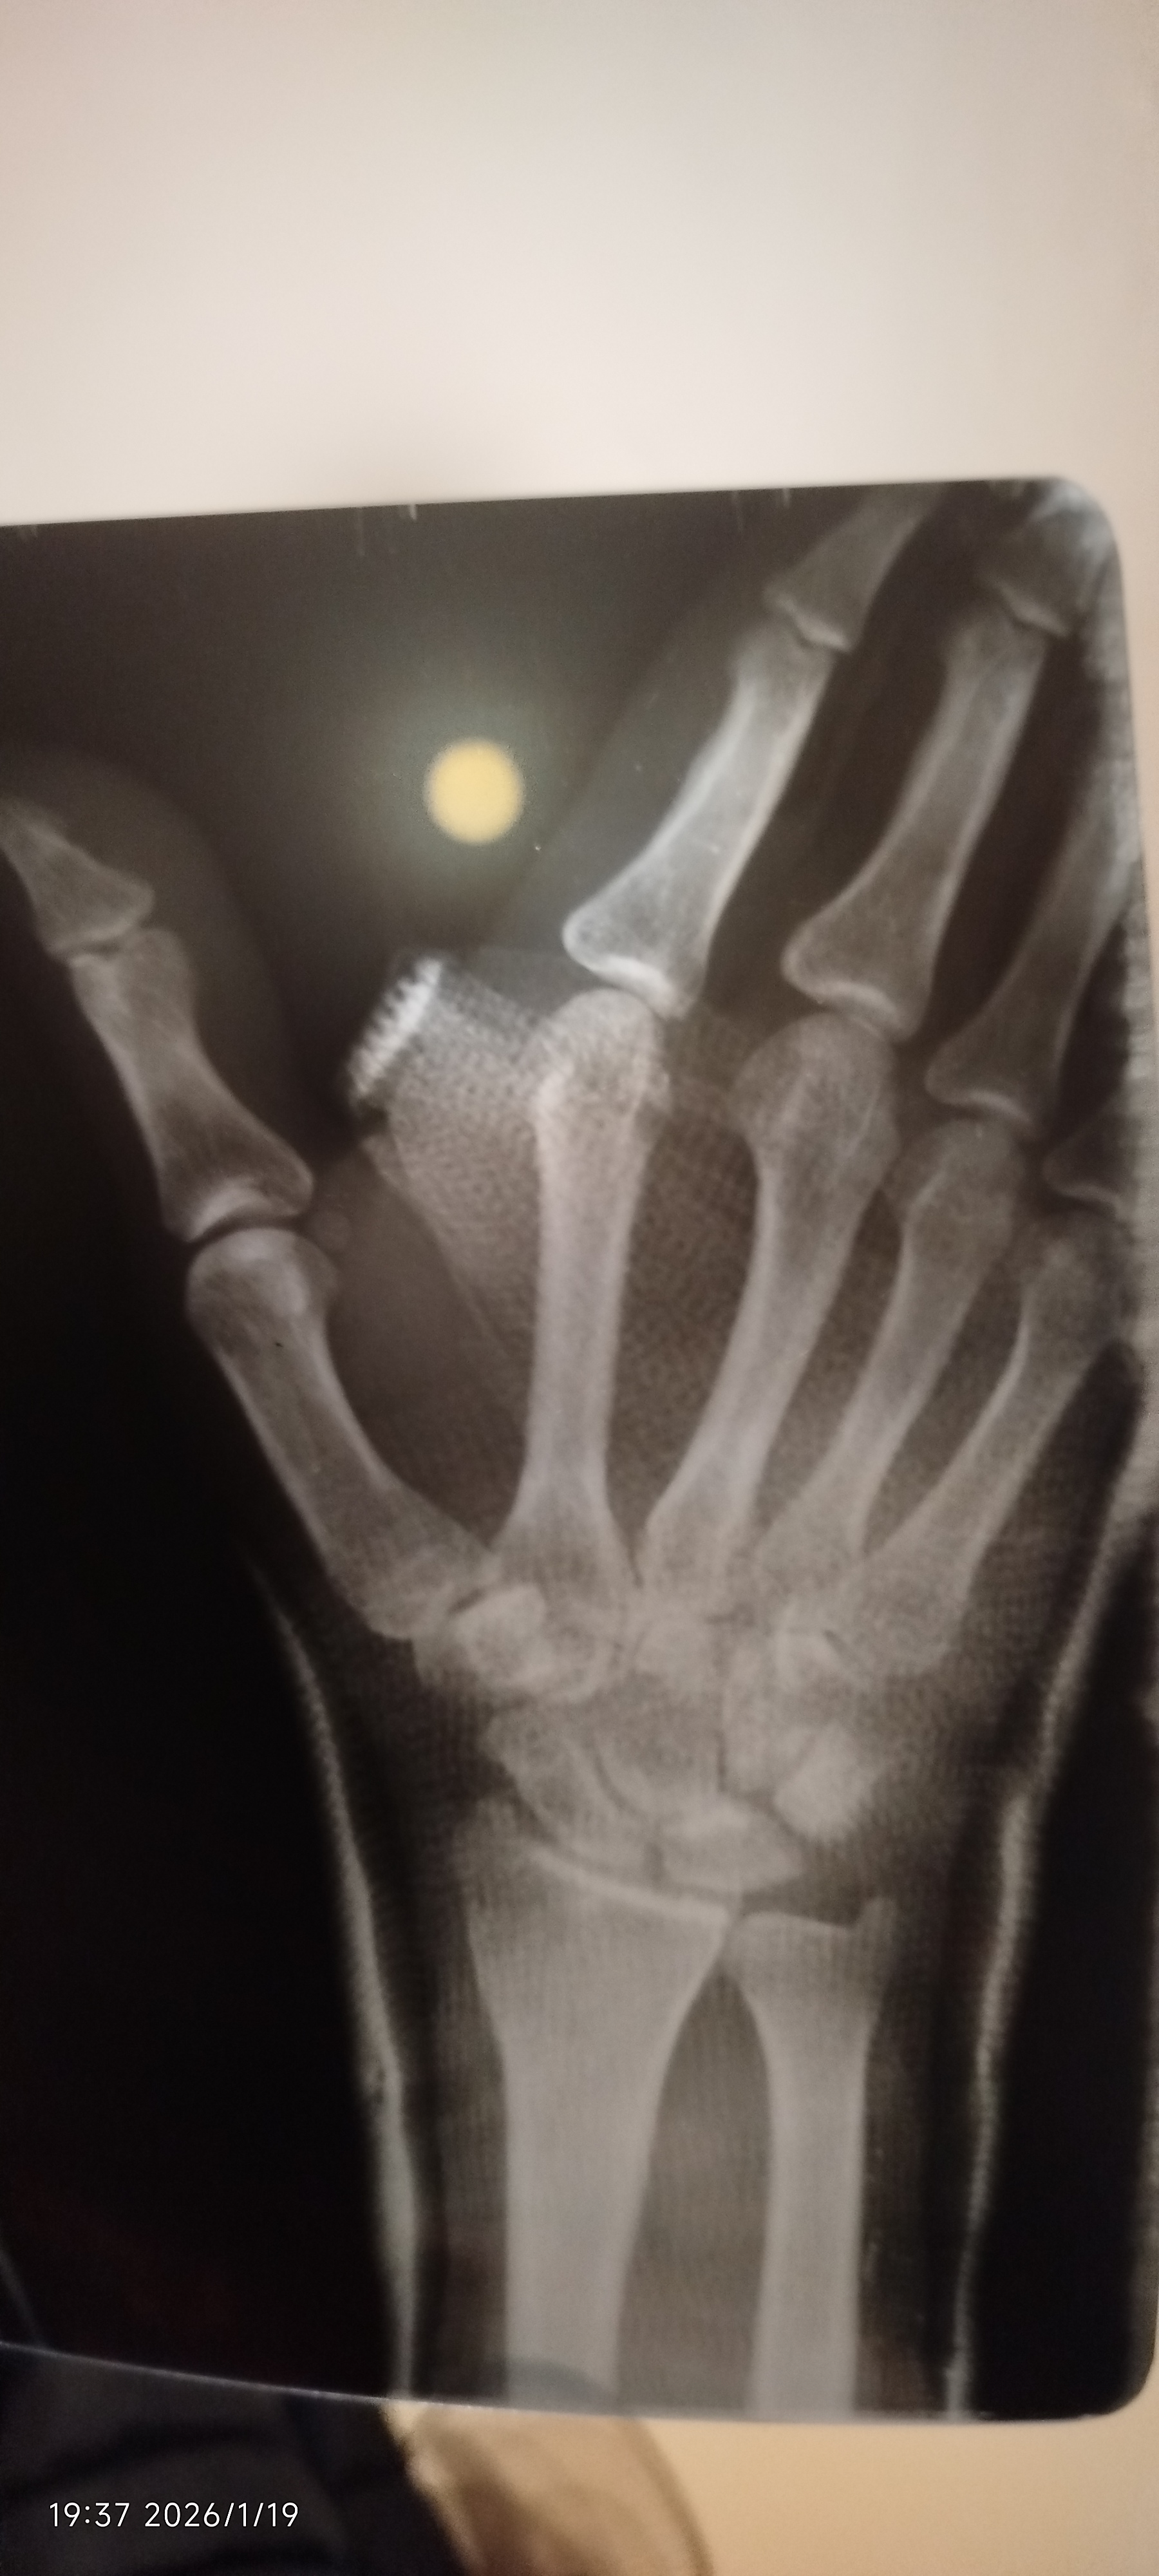

كسر في العضمه الزورقي

هل لسه في كسر في الاشاعه وهل العضم في مكانه الطبيعي